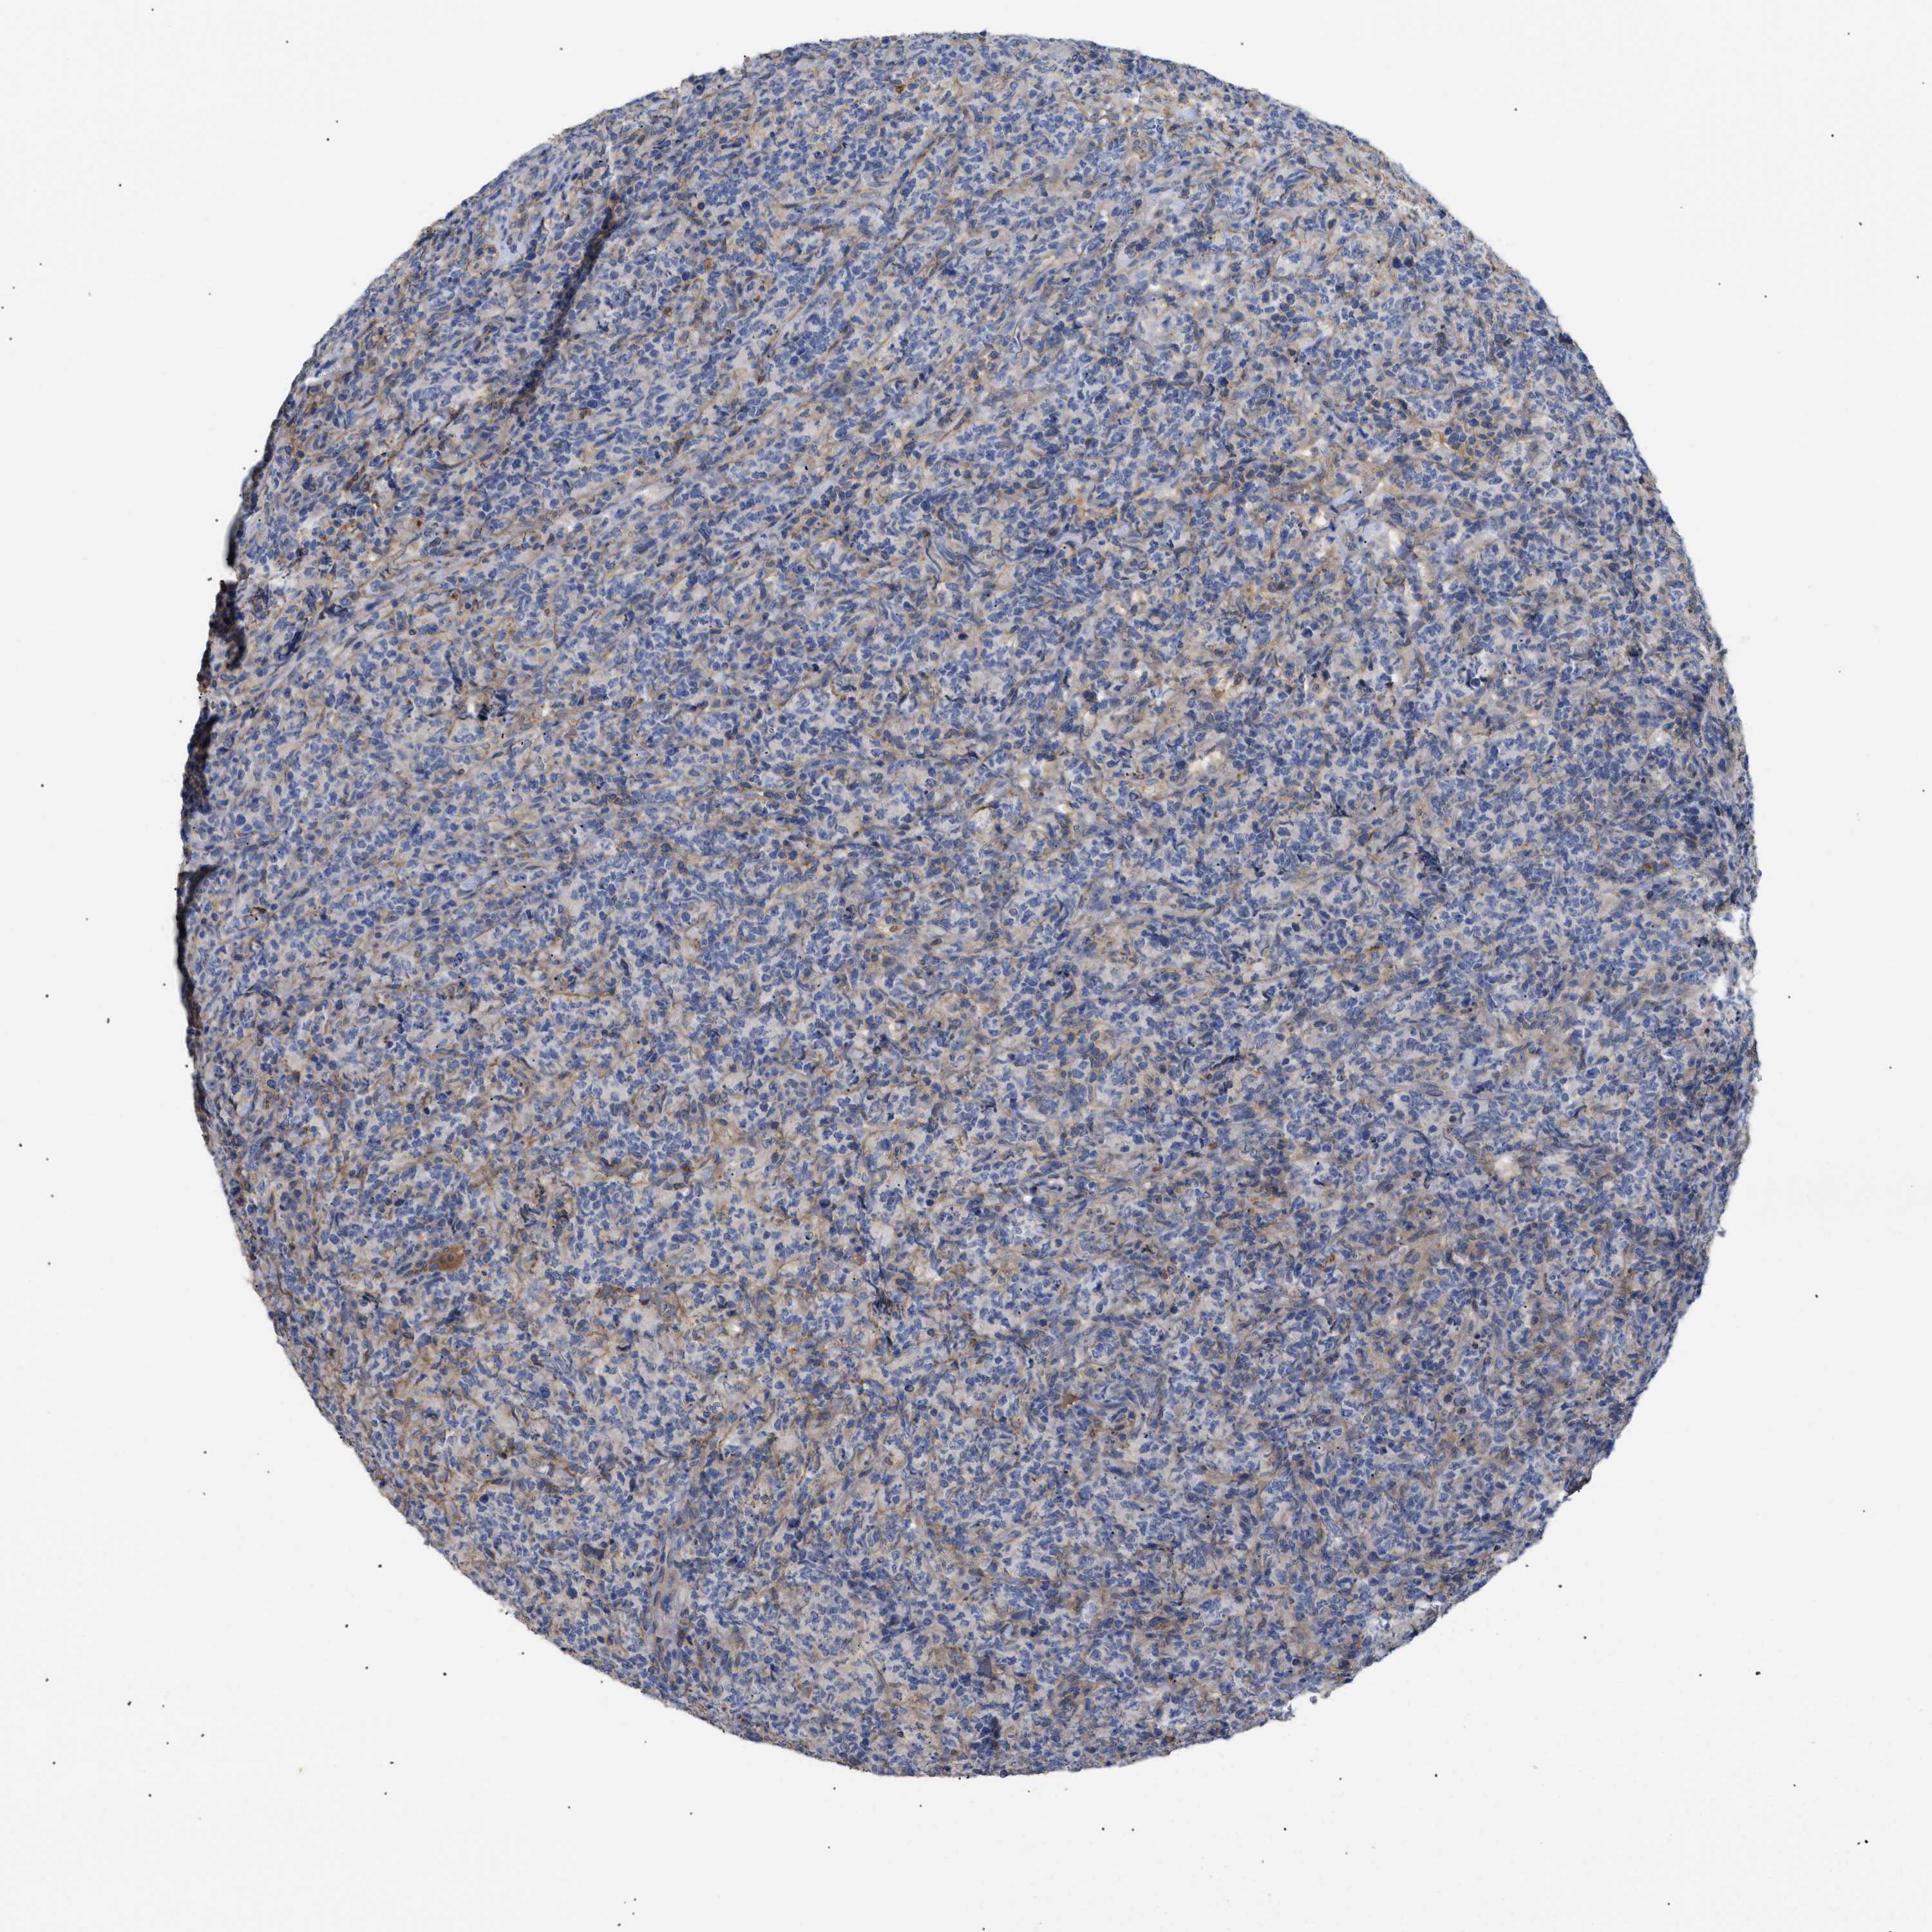

LYMPHOMA - Protein expressioni

A mouse-over function shows sample information and annotation data. Click on an image to view it in a full screen mode. Samples can be filtered based on level of antibody staining by selecting one or several of the following categories: high, medium, low and not detected. The assay and annotation is described here.

Antibody stainingi

Antibody staining in the annotated cell types in the current human tissue is reported as not detected, low, medium, or high, based on conventional immunohistochemistry profiling in selected tissues. This score is based on the combination of the staining intensity and fraction of stained cells.

Each image is clickable and will lead to virtual microscopy that enables deeper exploration of all samples and also displays staining intensity scores, fraction scores and subcellular localization as well as patient and tissue information for each sample.

Antibody HPA007393

Antibody CAB005076

Antibody CAB017560

Staining

High

Medium

Low

Not detected

Intensity

Strong

Moderate

Weak

Negative

Quantity

>75%

75%-25%

<25%

None

Location

Nuclear

Cytoplasmic/membranous

Cytoplasmic/membranous,nuclear

Hodgkin's disease, NOS

Malignant lymphoma, non-Hodgkin's type, High grade

Malignant lymphoma, non-Hodgkin's type, Low grade